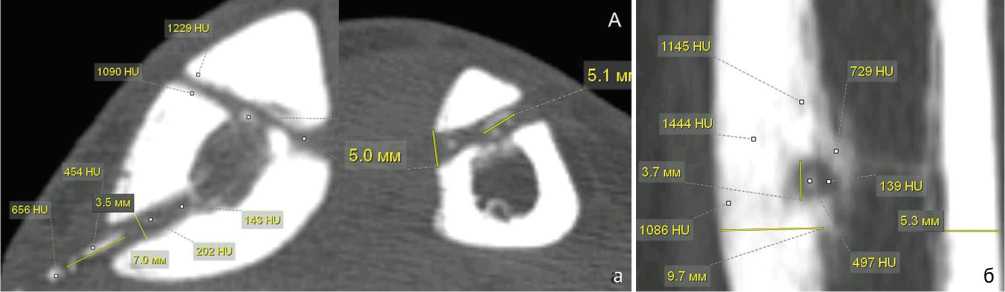

Плотность кости в проксимальном отделе метафиза большеберцовой кости на уровне спицевого канала колебалась в различных пределах: от (223,4 ± 25,8) HU до отрицательных значений шкалы Ха-унсфилда, преимущественно в центральных отделах метафиза. Плотность стенок спицевого канала в метафизарных отделах всегда превышала плотность кости, — (376,7 ± 85,4) HU, достигая в некоторых участках (792,8 ± 69,7) HU ( p < 0,02). Содержимое спицевого канала имело меньшую плотность, не превышая (179,4 ± 65,7) HU. В ряде случаев плотность содержимого спицевого канала была значительно меньше, — (12,5 ± 3,8) HU (рис. 1).

Рис. 1. МСКТ голени пациентки 50 лет со СО, аксиальные срезы: а — определение плотности кости и содержимого спицевого канала; б — определение плотности стенок спицевого канала